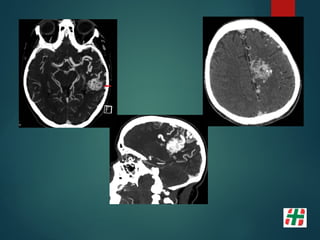

Hematoma

Hipertensivo

 ¿Cual esel mejor estudio para descartar hemorragia?  TC IA  RM con GRE IB  * GRE gran sensibilidad para detectar microhemorragias invisibles para la TC.  Menos de 5 no cambian la evolución.  Mas de 5 NO hay evidencia que empeore el pronóstico (mayor tasa de sangrados)

• 66.